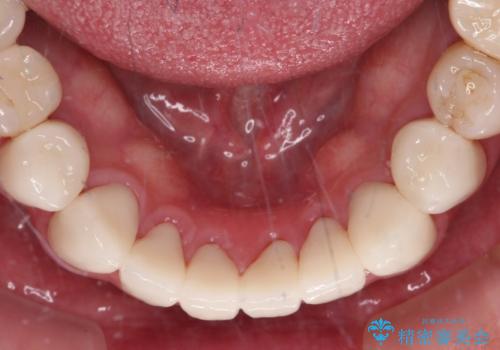

憧れの白い歯に 全顎セラミック治療

- 60歳を越え、黄ばんだ前歯をセラミッククラウンできれいな口元にしたいとのことで来院された患者様です。

診察したところ、前歯は反対咬合であり、その影響で抜歯が必要な奥歯があることが分かりました。

抜歯が必要な奥歯は、インプラント並びにブリッジにより補綴を行い、上下前歯は反対咬合を改善させるように補綴治療を行うこととしました。

健全な歯を削ってセラミッククラウンに置き換えることは、本来避けるべき治療と考えますが、今回は①患者様が60歳を越えていること、②要改善の咬合により抜歯が必要な奥歯があること、③反対咬合の前歯改善の手段としてセラミック治療が選択肢にあることなどから、全顎的なセラミック治療を行うこととしました。